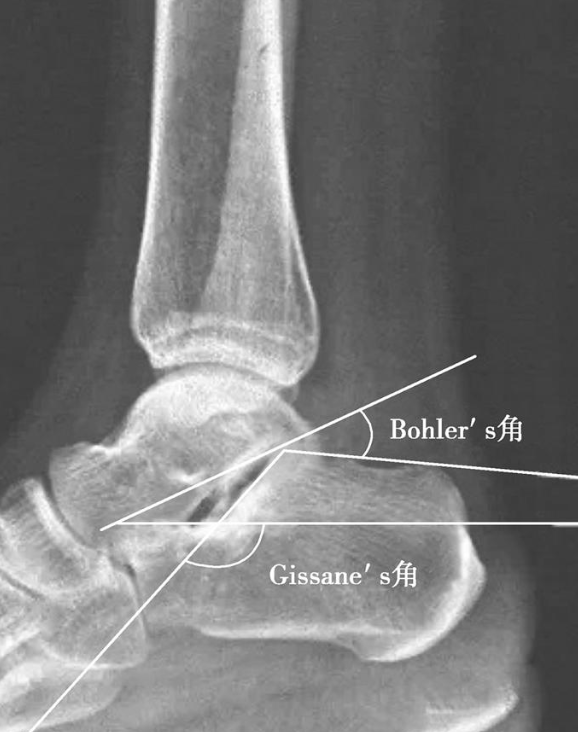

Böhler角:又称跟骨结节角,正常范围在25°~45°之间,此角缩小表明承重面及后关节面有压缩、下陷(图1)。

结节关节(Gissane)角:正常范围在125°~145°之间,跟距关节内骨折常造成此角增大或缩小(图1)。

图1 Böhler角及Gissane角